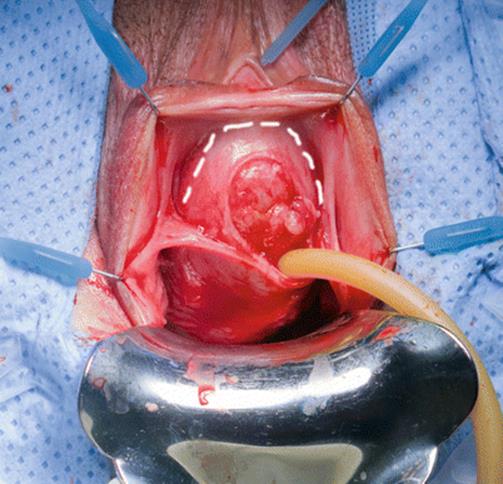

Fig. 8.50

The distal and proximal urethras are wide open (like a cone with the tip representing the bladder neck). The bladder neck is the only area intact and competent. Construction of a neourethra will be performed

Fig. 8.51

Two parallel incisions (broken white line) are made in the anterior, widely dilated defect of the urethral wall, lateral to the Foley catheter, starting at the bladder neck